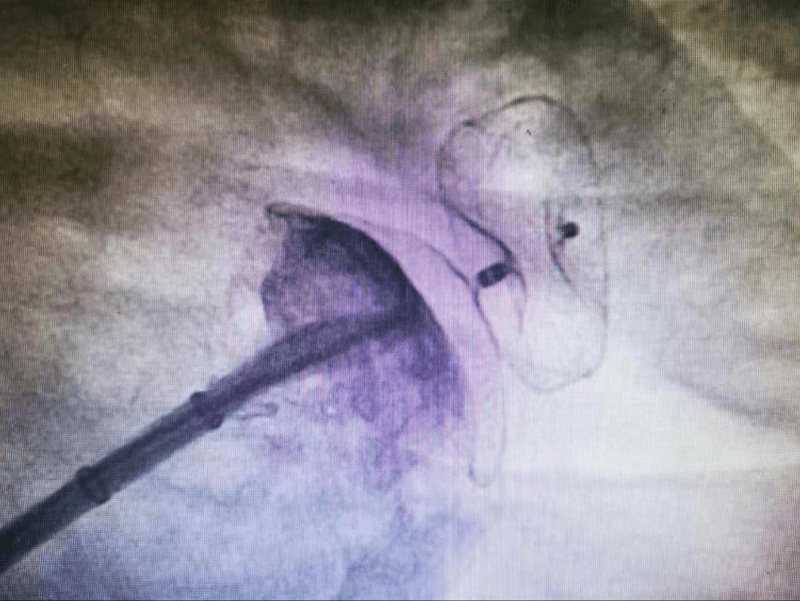

同时 , 检查提示 , 陈女士心房过大 , 房颤有一定复发率;并且陈女士为非瓣膜性房颤(此类患者尤其容易在左心耳形成血栓) , 她的左心耳开口直径达34mm , 呈菜花状 , 梳状肌发达 , 这是所有心耳形态中血栓形成风险最高者 。 因此建议射频消融联合左心耳封堵术 , 针对血栓形成部位——左心耳进行封堵 , 避免未来血栓栓塞 , 大大降低卒中风险 。 两者完美结合 , 一站式解决房颤危害 。

陈女士及家属接受了治疗新方案 , 却又遇到了新的难题 。 由于陈女士左心耳开口直径过大 , 常用的封堵器没有合适型号 。 心内科医护团队尽全力救治患者 , 经区文超教授及林晓圳副主任医师反复与多方沟通 , 为陈女士量身定制了适合其自身情况的双盘封堵器!

由于术前检查发现陈女士左心耳开口位置偏低且靠前 , 距离心脏的“阀门”——二尖瓣较近 , 手术中有可能存在损伤二尖瓣、残余漏、封堵不成功等风险 , 大大增加了手术难度 。

心内科医护团队迎难而上 , 区文超教授与林晓圳副主任医师反复确认手术流程、评估所有可能风险、做好充分预案 , 为陈女士于局麻下行手术治疗 , 选择双盘状封堵器 , 采用“三明治”封堵策略 , 封堵后多角度观察无残余分流 , 牵拉封堵器固定稳妥 , 食道超声检查封堵良好 , 一次性封堵成功 。